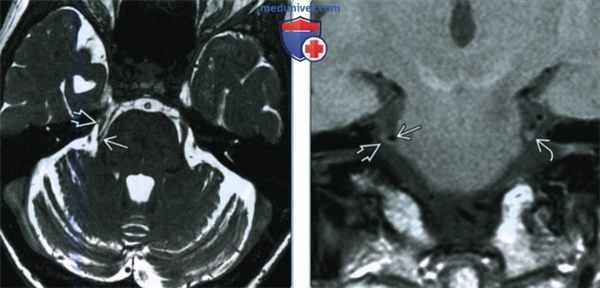

(Слева) При аксиальной МРТ Т2 ВИ у пациента с правосторонней тригеминальной невралгией (ТН) визуализируется гипоинтенсивная верхняя мозжечковая артерия, воздействующая на зону входа корешка в области преганглионарного сегмента тройничного нерва.

(Справа) При корональной МРТ Т1 ВИ у этого же пациента визуализируется верхняя мозжечковая артерия, сдавливающая и деформирующая проксимальный преганглионарный сегмент правого ЧН V. Слева преганглионарный ЧН V не изменен, имеет большие размеры, что свидетельствует об атрофии ЧН V справа.